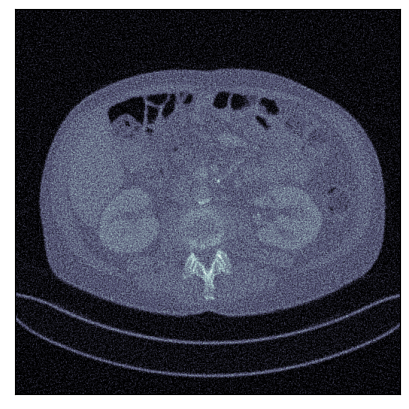

Refer to captionRefer to caption

Ground-truth

FBP: 21.303 dB, 0.195

TV: 31.690 dB, 0.889

U-Net: 36.712 dB, 0.920

LPD: 36.810 dB, 0.912

AR: 36.694 dB, 0.907

ACR: 35.708 dB, 0.897

ACNCR: 36.533 dB, 0.921

AWCR: 37.603 dB, 0.918

AWCR-PD: 37.941 dB, 0.924

Figure 2: Reconstructed images obtained using different methods, along with the associated PSNR and SSIM, for sparse view CT. In this case the AWCR and AWCR-PD achieve the highest PSNR and SSIM. Furthermore, both AWCR methods retain the fine-structure in the reconstruction, unlike the ACNCR and ACR, the only other methods which possess convergence guarantees.

These comparisons illustrate the trade-offs in levels of constraints and supervision versus stability and performance. For details of the experimental set-up, see Section G.1. We measure the performance in terms of the peak signal-to-noise ratio (PSNR) and the structural similarity index (SSIM) [Wang et al., 2004]. We report average test dataset results in Table 1, with further visual examples in Figure 2.

Sparse view CT As in [Lunz et al., 2018] performance of AR during reconstruction begins to deteriorate if the network is over-trained, so early stopping must be employed in training. For the ACR, ACNCR, and both AWCR methods this does not occur due to reduced expressivity, yet both AWCR methods surpass the performace of AR. Indeed, the AWCR-PD method approaches the PSNR accuracy of the strongly supervised U-Net post-processing method.